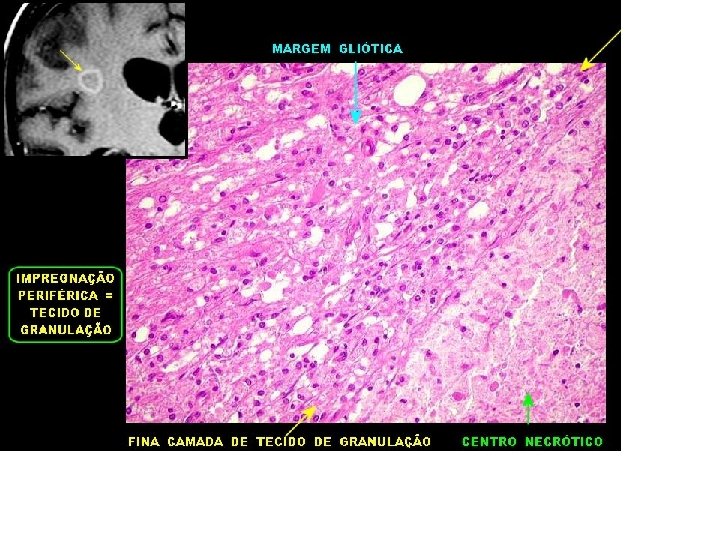

Toxoplasmose A grande maioria dos pequenos vasos intracorticais mostram proliferação e reduplicação das camadas, não sendo possível distinguir entre média e íntima. Na vasculite os microrganismos parasitam as células endoteliais, que morrem, sendo substituídas por outras. No processo há espessamento da parede, produção de várias camadas de membrana basal e fibras reticulínicas com conseqüente redução ou oclusão da luz. A obliteração vascular generalizada leva a necrose coagulativa. Habitualmente, a necrose isquêmica do cérebro é liqüefativa, como no infarto.

ENDARTERITE OBLITERANTE - NEUROTOXO

Muito espessada por fibrose. Os vasos freqüentemente mostravam endarterite obliterante, com grande espessamento da íntima e redução ou obliteração da luz.